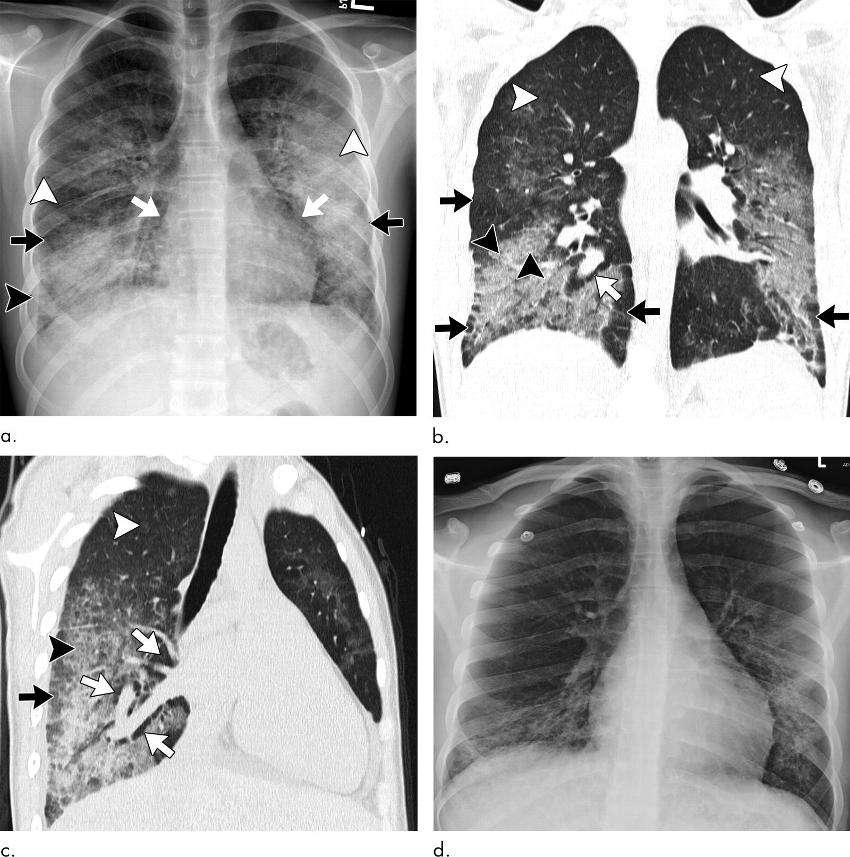

Figure 4. Images show electronic cigarette or vaping product use–associated lung injury with organizing pneumonia pattern in an 18-year-old man who vaped nicotine and tetrahydrocannabinol with fever of 103°F, vomiting for 3 days, and negative workup for infection and rheumatologic disease. (a) Posteroanterior radiograph shows perihilar predominant hazy opacity with conspicuous sparing of both heart border (white arrows) and periphery (black arrows). Septal thickening is present (arrowhead). (b) Corresponding CT image shows perihilar predominant ground-glass opacity with prominent sparing of subpleural interstitium both peripherally and centrally (black arrows) with intermixed areas of lobular sparing. In addition, there is sparing of peribronchovascular interstitium (white arrows). Septal thickening (black arrowhead) and scattered centrilobular nodules are present (white arrowhead). Patient rapidly improved after administration of steroids.

Figure 5. Images show electronic cigarette or vaping product use–associated lung injury with organizing pneumonia pattern in a 20-year-old man who vapes nicotine and tetrahydrocannabinol products daily and who presented to community health clinic with fever, weakness, and chills. He was initially diagnosed with community-acquired pneumonia, but his symptoms continued to progress despite antibiotic therapy. Extensive work-up for infection and rheumatologic disease was negative during hospital admission. (a) Axial CT image shows peribronchiolar ground-glass opacity with subpleural sparing both centrally and peripherally (black arrows). Few areas of bronchial dilation are present in areas of ground-glass opacity (white arrow). Bronchoscopic biopsy yielded result of organizing pneumonia. (b) Four weeks after initiation of steroid therapy, patient’s CT scan was normal.